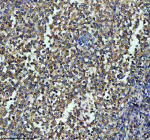

Immunohistochemical staining of ITGB7 using anti-ITGB7 antibody. ITGB7 was detected in a paraffin-embedded section of mouse spleen tissue. Heat mediated antigen retrieval was performed in EDTA buffer (pH 8.0, epitope retrieval solution). The tissue section was blocked with 10% goat serum. The tissue section was then incubated with 1:50 rabbit anti-ITGB7 antibody overnight at 4oC. Peroxidase Conjugated Goat Anti-rabbit IgG was used as secondary antibody and incubated for 30 minutes at 37oC. The tissue section was developed using an HRP secondary and DAB substrate.